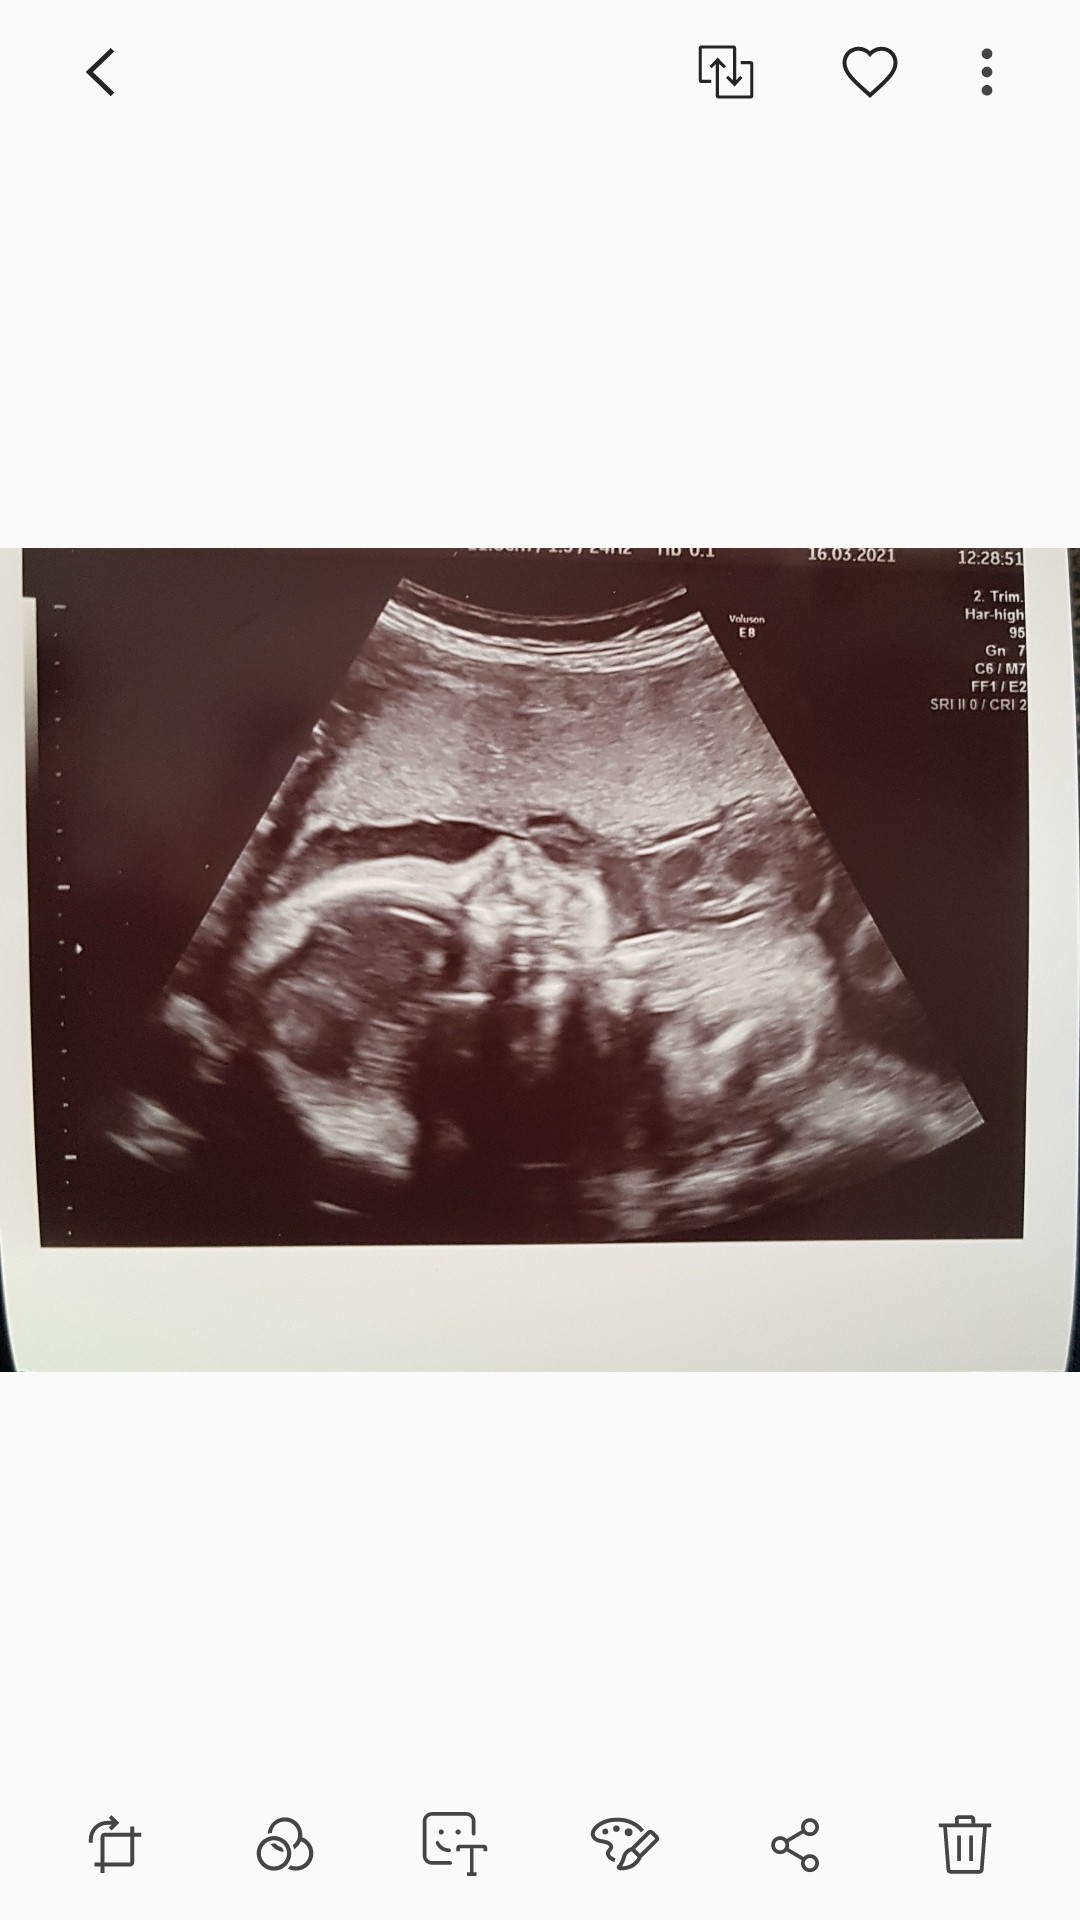

Licząc na kalkulatorze wychodzi ze z data transferu jest 6+4 a z ost miesiączki 6+3Ciążę się liczy od ostatniej miesiączki ale przy transferach to różnie może być niektóre mają już w 15dc transfer.. Dlatego najlepiej wyliczyć sobie wiek zarodka plus 2 tygodnie i wtedy wpisać ta date jako dzień ostatniej miesiączki do kalendarza obliczajeco wiek ciąży